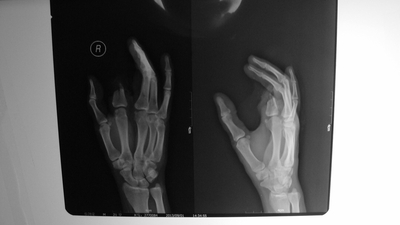

断指再植案例

2岁宝宝右手的中指被机器挤压撕脱离断,环指末节脱套指骨外漏,血管神经抽剥离断,中指屈伸肌腱从前臂抽离,手背可见5厘米纵形挫裂伤口,手术后孩子的中指再植及环指皮肤撕脱修复都已存活。